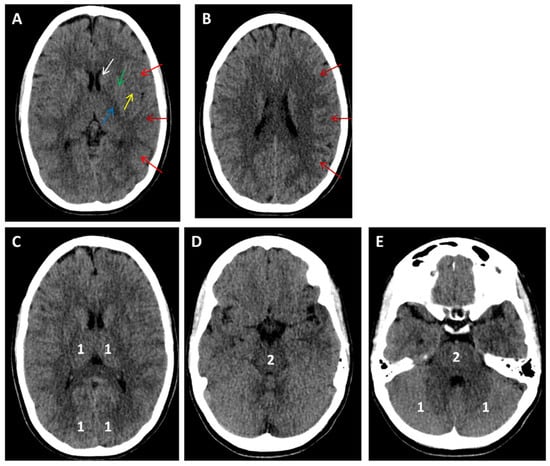

- Puetz, V.; Khomenko, A.; Hill, M.D.; Dzialowski, I.; Michel, P.; Weimar, C.; Wijman, C.A.; Mattle, H.P.; Engelter, S.T.; Muir, K.W.; et al. Extent of hypoattenuation on CT angiography source images in basilar artery occlusion: Prognostic value in the Basilar Artery International Cooperation Study. Stroke 2011, 42, 3454–3459. [Google Scholar] [CrossRef] [PubMed]

- Schaefer, P.W.; Yoo, A.J.; Bell, D.; Barak, E.R.; Romero, J.M.; Nogueira, R.G.; Lev, M.H.; Schwamm, L.H.; Gonzalez, R.G.; Hirsch, J.A. CT angiography-source image hypoattenuation predicts clinical outcome in posterior circulation strokes treated with intraarterial therapy. Stroke 2008, 39, 3107–3109. [Google Scholar] [CrossRef]